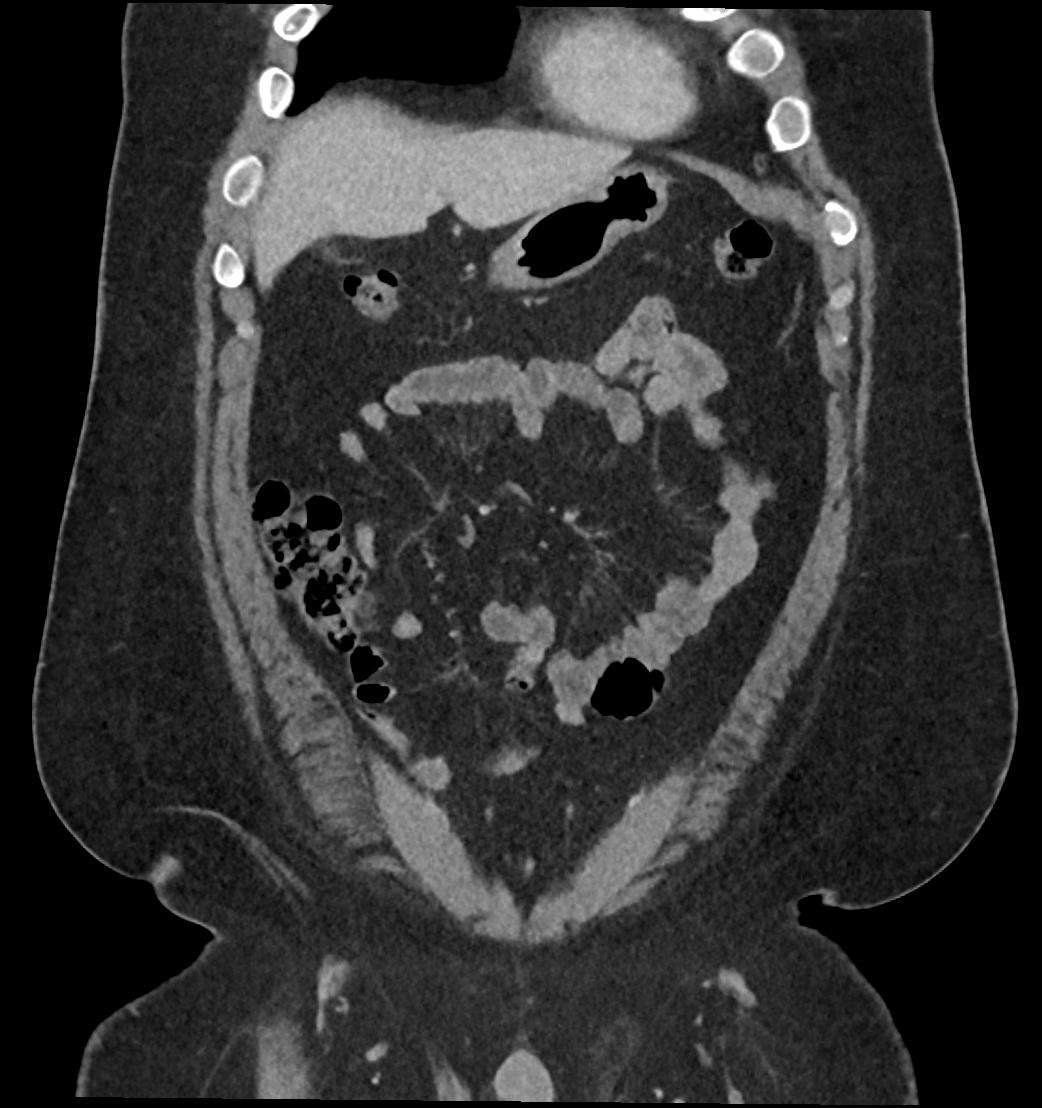

Patient: Padmakumar A. , *1988-04-24, PID: 3000069741773230809

Study Description: CT ABDOMEN

Image Series: Abdomen Cor 3mm [4]

<< Previous | Image 39 of 119 | Next >>